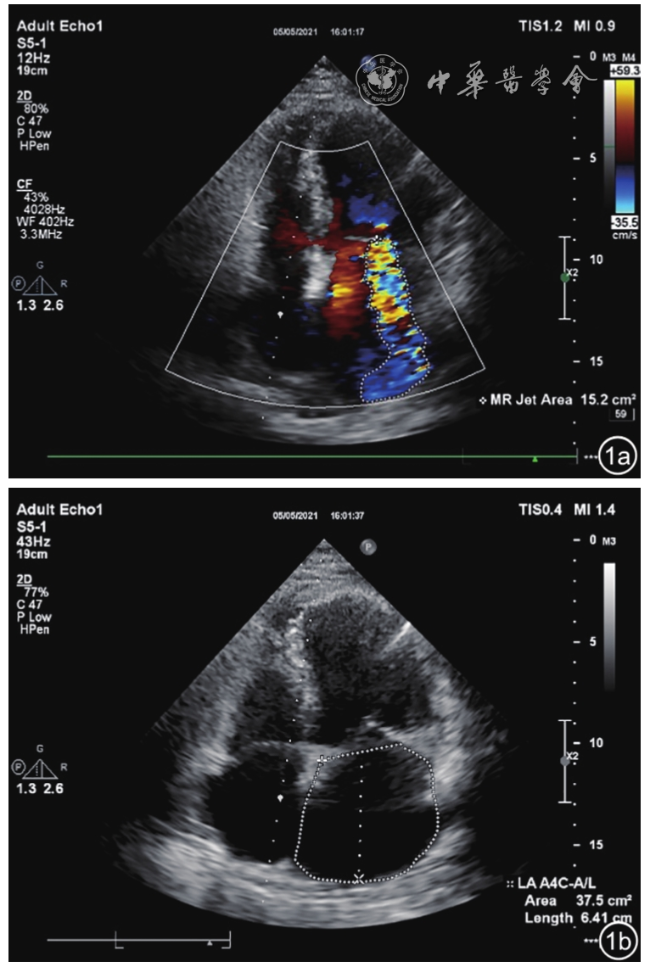

3. 近端等速表面积(proximal isovelocity surface area,PISA):PISA方法是目前超声心动图评估FMR较为常用的定量方法,也是较为可靠的超声指标15。其评估方法如下:EROA=2πr2×Va/Peak V(MR),RV=EROA×TVI(MR)(EROA:有效反流口面积;Peak V(MR):二尖瓣反流的峰值流速;Va:混叠速度;RV:反流量;TVI:二尖瓣反流时间-速度积分)。反流分数(RF)=RV/SV(SV:左心室每搏量)(图3)。轻度MR:EROA<0.20 cm2,RV<30 ml,反流分数<30%;重度MR:EROA≥0.40 cm2,RV≥60 ml,RF≥50%;中度MR:0.20 cm2≤EROA<0.40 cm2,30 ml≤RV<60 ml,30%≤RF<50%。PISA对中心性反流的测量较偏心性反流更为精确,对圆形反流口测量较非圆形反流口更为精确。在美国超声心动图学会(American Society of Echocardiography,ASE)指南12中,重度FMR与重度原发性MR相似,被定义为EROA≥0.4 cm2和RV≥60 ml。由于FMR中EROA是半月形而不是原发性MR中的圆形,因此FMR患者的EROA可能被低估。有随访研究表明,FMR患者的EROA在0.20~0.40 cm2之间同样提示临床预后不良16, 17。因此,2012年欧洲心脏病学会(European Society of Cardiology,ESC)指南18中,将重度FMR患者的EROA截断值由0.4 cm2降低至0.2 cm2

图3 二维超声心动图测量二尖瓣反流率、反流量及有效反流口面积。图a为二维超声心动图将底部尼奎斯特极限调至30~40 cm/s,在大致达到连续多普勒血流的峰值时测量近端等速表面积(PISA)半球形的半径r,根据位于瓣口的极限速度v,可计算出反流率为196 ml/s;图b根据二尖瓣反流连续多普勒频谱,测算得出有效反流口面积为0.33 cm2,反流量为45 ml